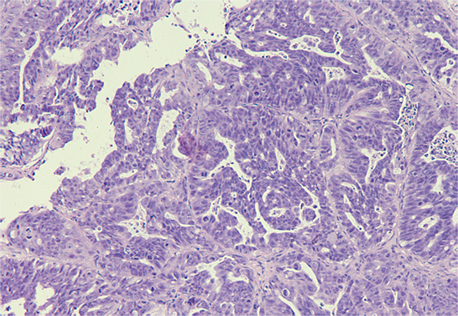

PDX Model (MED-PDX-001C H&E (10X))